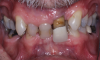

(7.) Pretreatment retracted view of a 60-year-old male patient who presented to receive comprehensive care and full-mouth rehabilitation to enhance his function, stability, and esthetics. Due to his malocclusion at the time of presentation, adult orthodontic treatment was recommended. Given the patient’s anterior deep vertical overlap, the decision was made to temporarily challenge his vertical dimension of occlusion to facilitate ease of bracketing the mandibular anterior teeth. This was to be achieved with posterior full-coverage composite crowns.

Figure 7